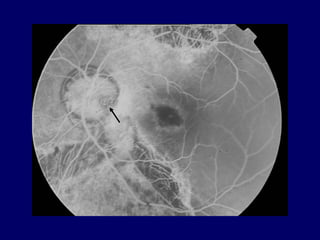

FLUOROGRAPHIC FEATURES

 Early hypofluorescence

 Late hyperfluorescence due to leakage at the

margins of, or from the depth of the pit.

 RPE window defects are observed with RPE atrophy